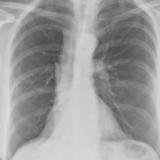

RLL Collapse 1 PA